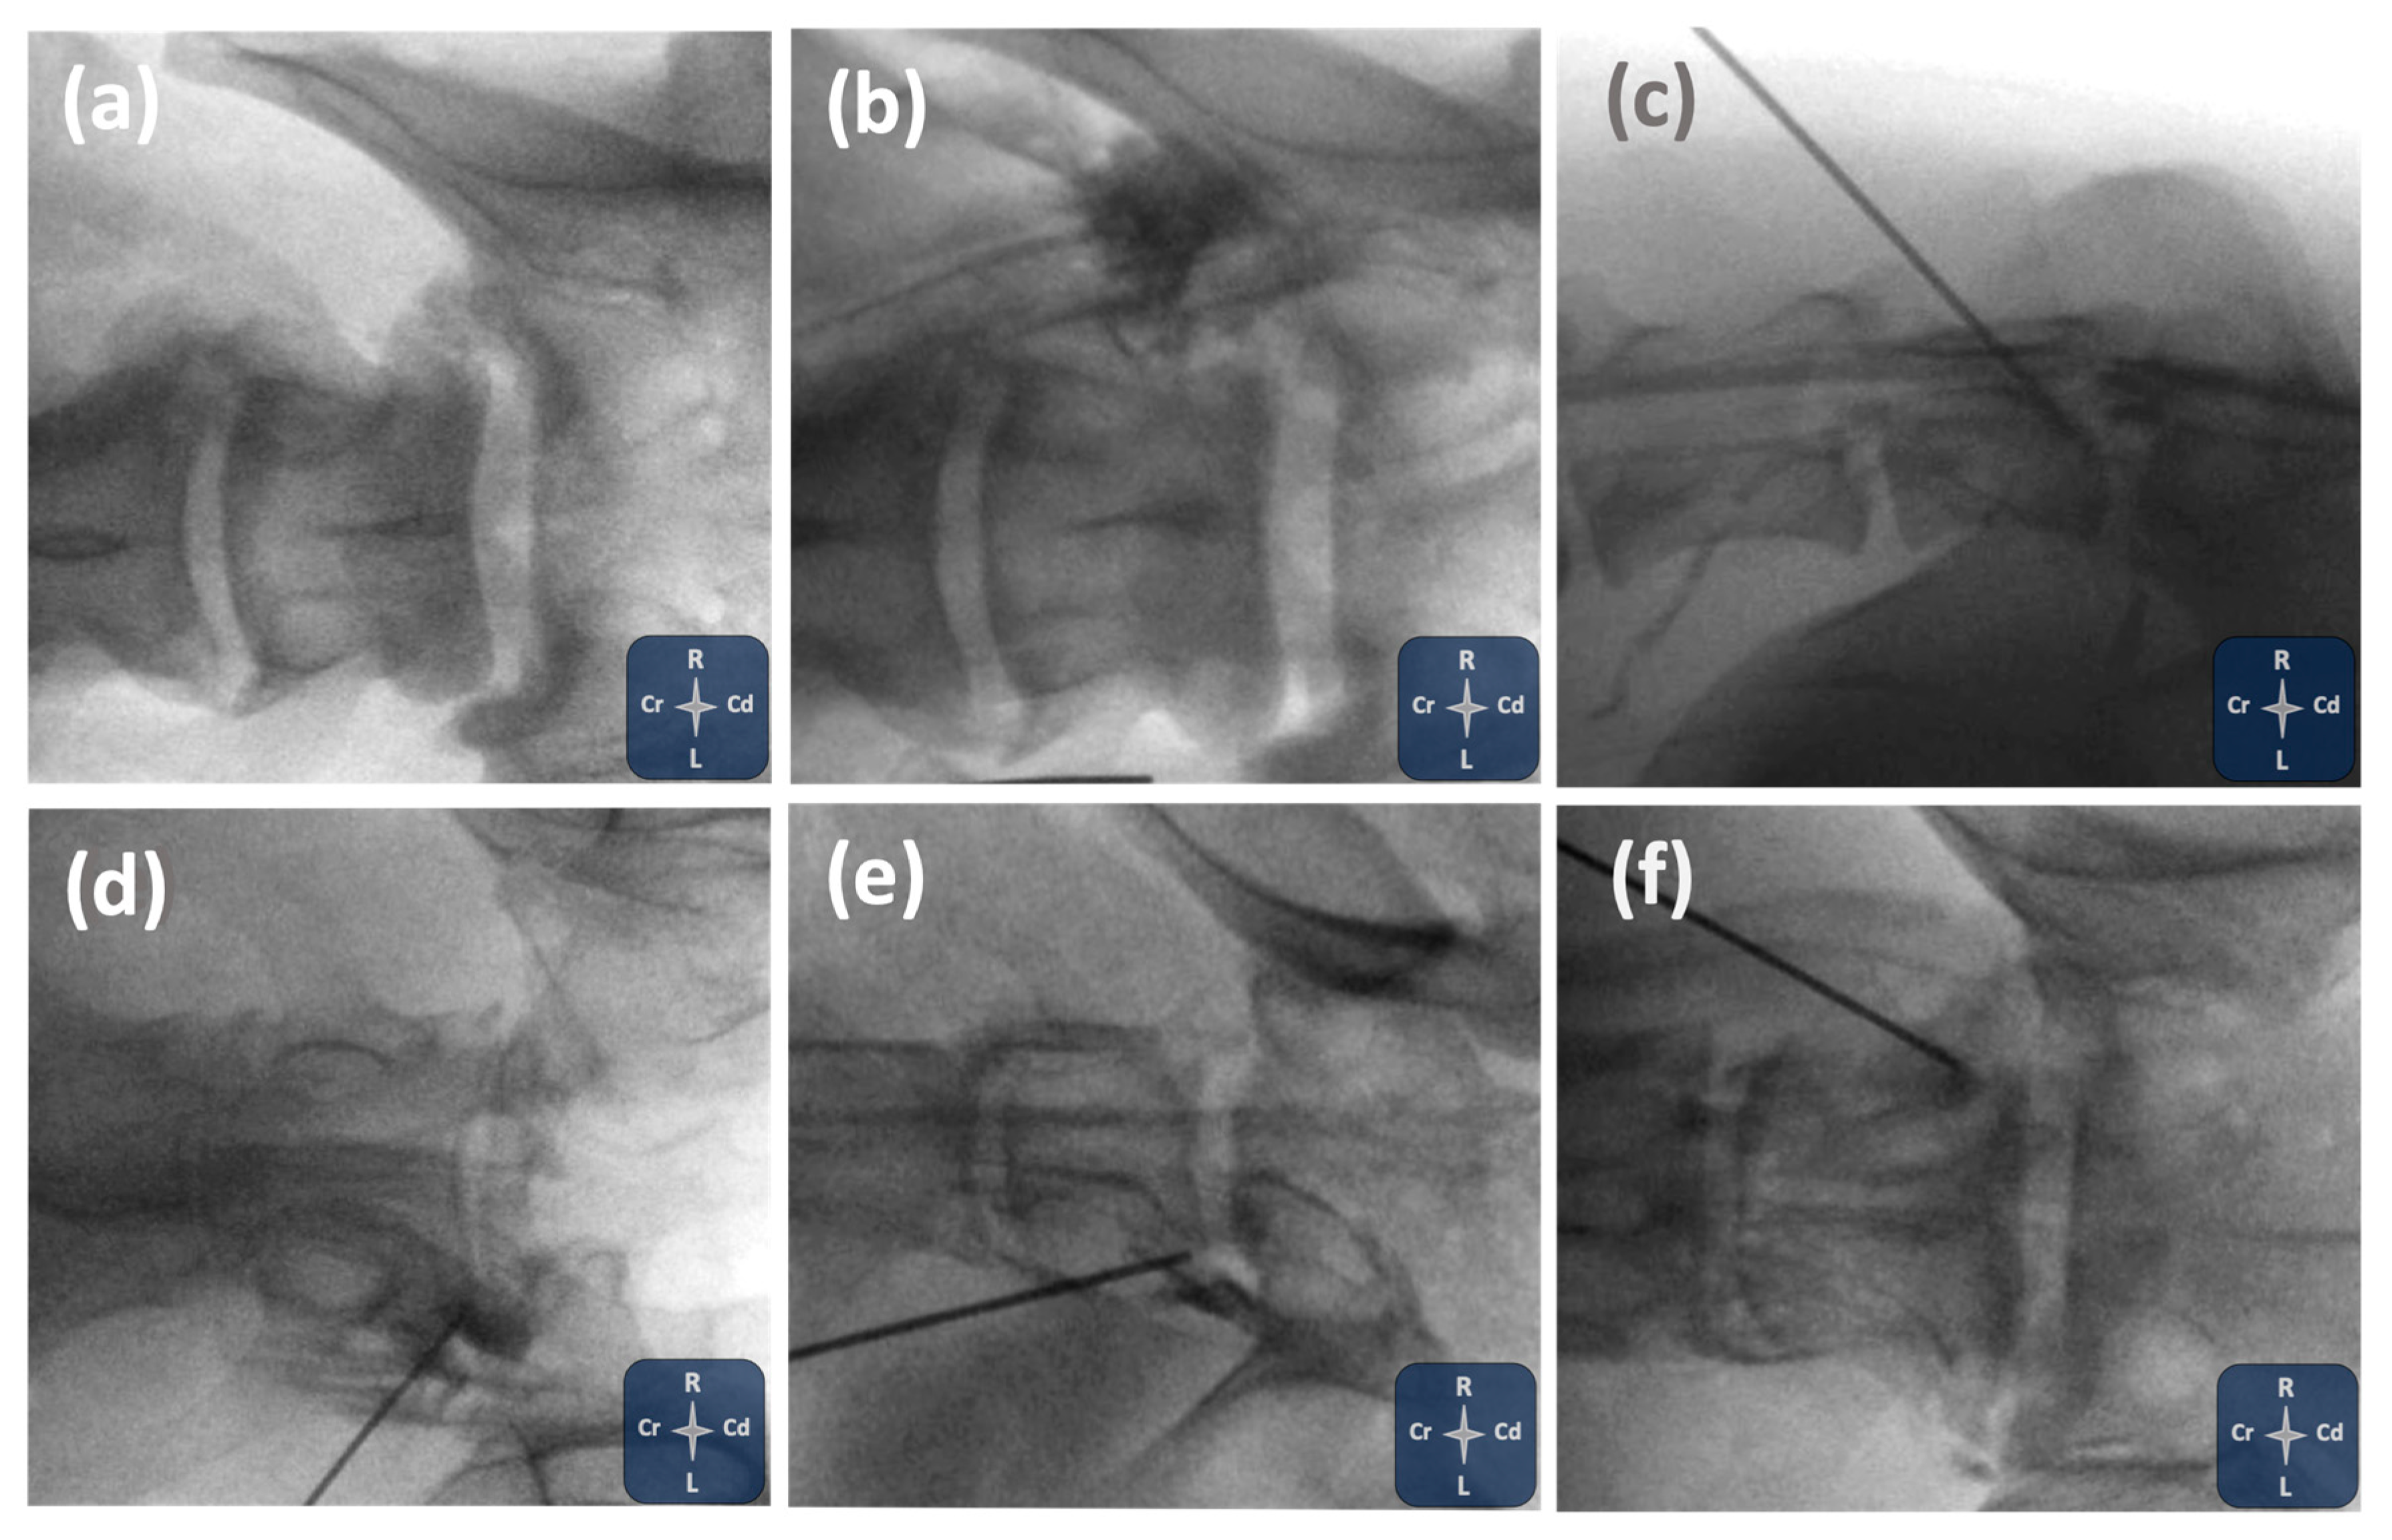

2.1. Phase I: Ultrasound- and Fluoroscopy-Guided Technique

3.1. Phase I: Ultrasound- and Fluoroscopy-Guided Technique